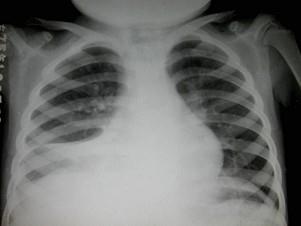

问题 女,6岁,低热,盗汗,咳痰,呼吸困难1月余,结合图像,最可能的诊断是?(?)

选项 A.肺脓肿 B.大叶性肺炎 C.右肺中叶综合征 D.肺癌 E.胸腔积液

答案 C